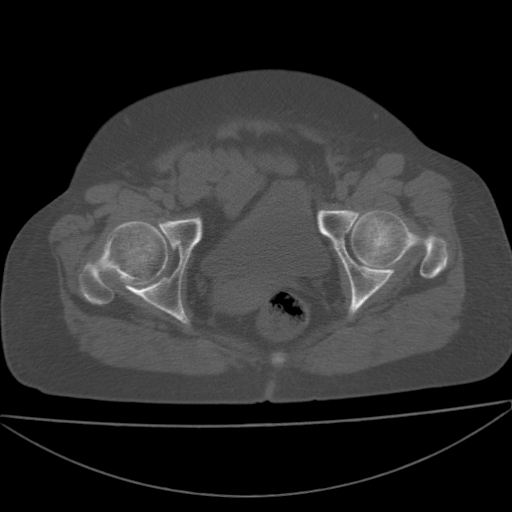

以下是引用余辉在2009-4-23 17:08:00的发言:[br]考虑右髋关节退行性变.股骨颈改变考虑陈旧性骨折可能,股骨头顶部关节面下似有透亮区,股骨头皮质环增厚,考虑有股骨头坏死

以下是引用王显瑞在2009-4-23 16:45:00的发言:[br]考虑股骨颈陈旧性骨折,股骨头缺血型坏死